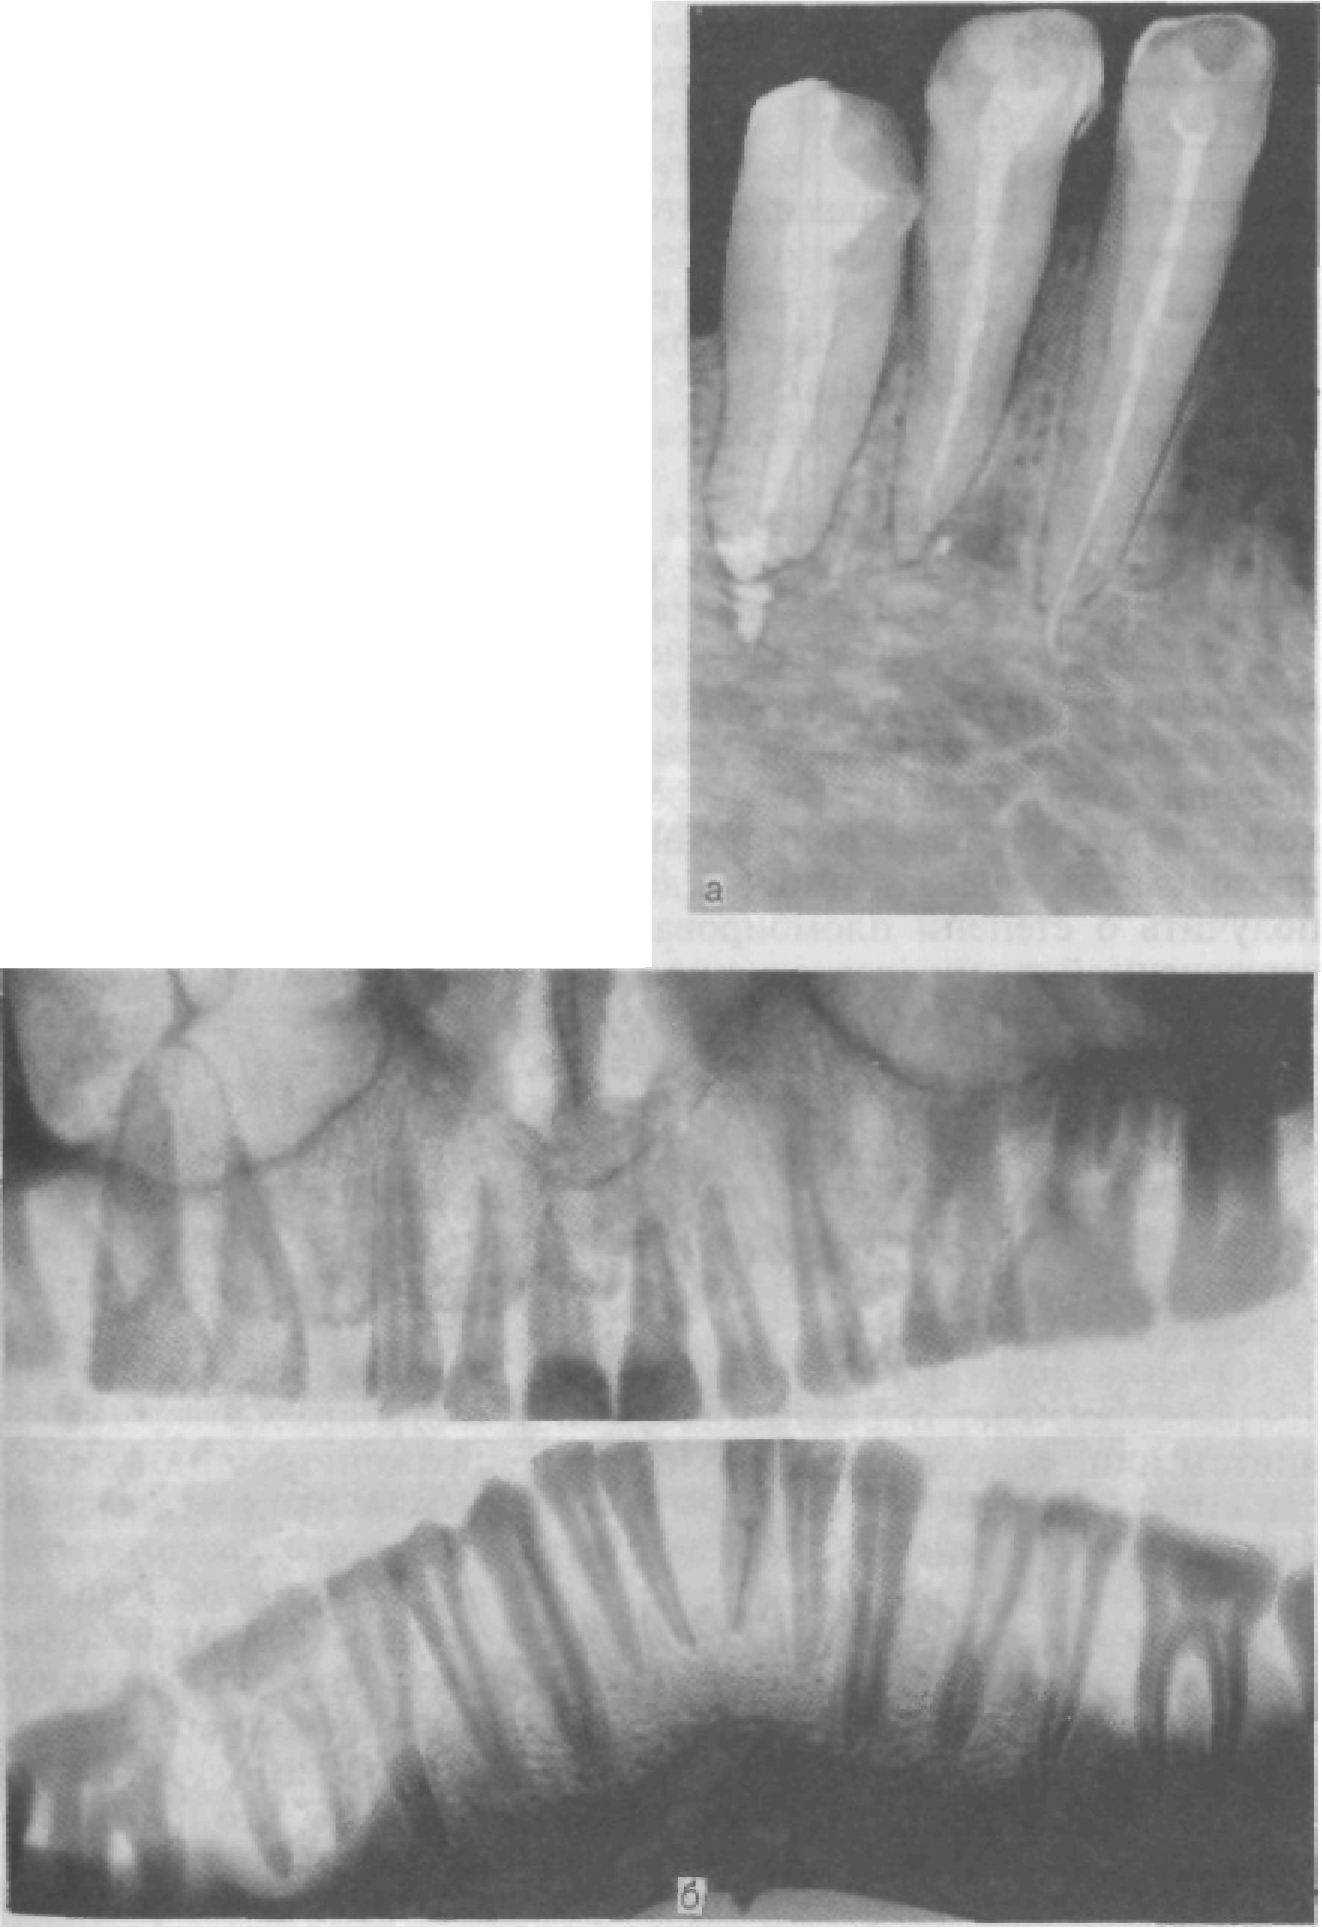

Внутриротовая рентгенограмма (рис. 56, а) дает возРис. 56. Внутриротовая (а) и панорамная (б) рентгенограммы

можность установить кариозные полости на проксимальных поверхностях, под искусственными коронками (но только в пришеечной зоне), наличие ретенированных зубов; при патологической стертости — ориентировочно топографию пульпы, степень проходимости каналов, наличие дентиклей. Важные данные можно получить о степени пломбирования каналов, состояния околоверхушечной ткани (разрежение костной ткани, гиперцементоз). Состояние периодонтальной щели, костной ткани альвеолярных отростков — стенок альвеол, включая замыкающую пластинку, рентгенографически можно определить только с боковых поверхностей корня зуба. Ни с вестибулярной, ни с язычной (небной) поверхности состояние околоверхушечных тканей, периодонтальной щели и стенок зубных альвеол выявить по рентгенограммам нельзя (рис. 57) (редкое исключение составляют случаи остеосклероза этих участков).